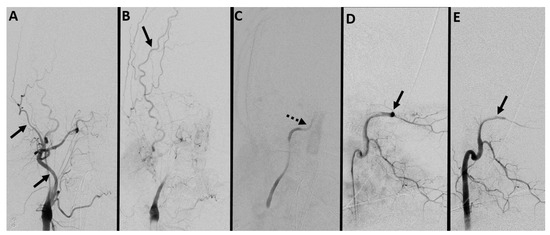

7.2. Digital Subtraction Angiography (DSA)

- Sawicki, M.; Bohatyrewicz, R.; Safranow, K.; Walecka, A.; Walecki, J.; Rowinski, O.; Solek-Pastuszka, J.; Czajkowski, Z.; Marzec-Lewenstein, E.; Motyl, K.; et al. Dynamic evaluation of stasis filling phenomenon with computed tomography in diagnosis of brain death. Neuroradiology 2013, 55, 1061–1069. [Google Scholar] [CrossRef] [PubMed]

- Alvarez, L.A.; Lipton, R.B.; Hirschfeld, A.; Salamon, O.; Lantos, G. Brain death determination by angiography in the setting of a skull defect. Arch. Neurol. 1988, 45, 225–227. [Google Scholar] [CrossRef] [PubMed]